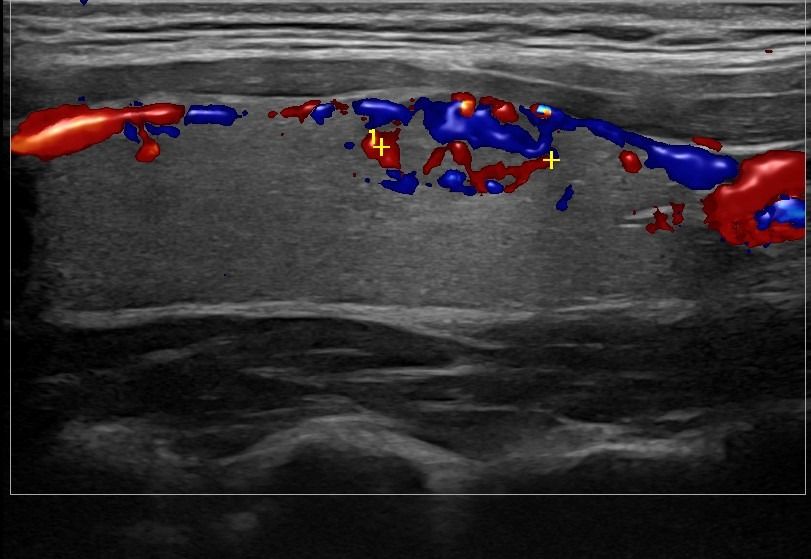

Με την τριπλή μελέτη του Θυρεοειδούς Αδένα, που περιλαμβάνει το B-Μode, το Έγχρωμο Υπερηχογράφημα και την Ελαστογραφία, γίνεται μια ολοκληρωμένη χαρτογράφηση του θυρεοειδούς αδένα. Το περίγραμμα, η αγγείωση και η ελαστικότητα του αδένα, καθώς και η υφή μίας πιθανής βλάβης αξιολογούνται με ακρίβεια και αξιοπιστία.

Πέραν των βασικών δομικών στοιχείων, το υπερηχογράφημα αποκαλύπτει πληροφορίες κρίσιμης σημασίας. Με αξιοσημείωτη ακρίβεια, ένας εξειδικευμένος Ιατρός- Ακτινολόγος ανιχνεύει και αξιολογεί:

• Εστιακές αλλοιώσεις (όζοι του θυρεοειδούς αδένα)